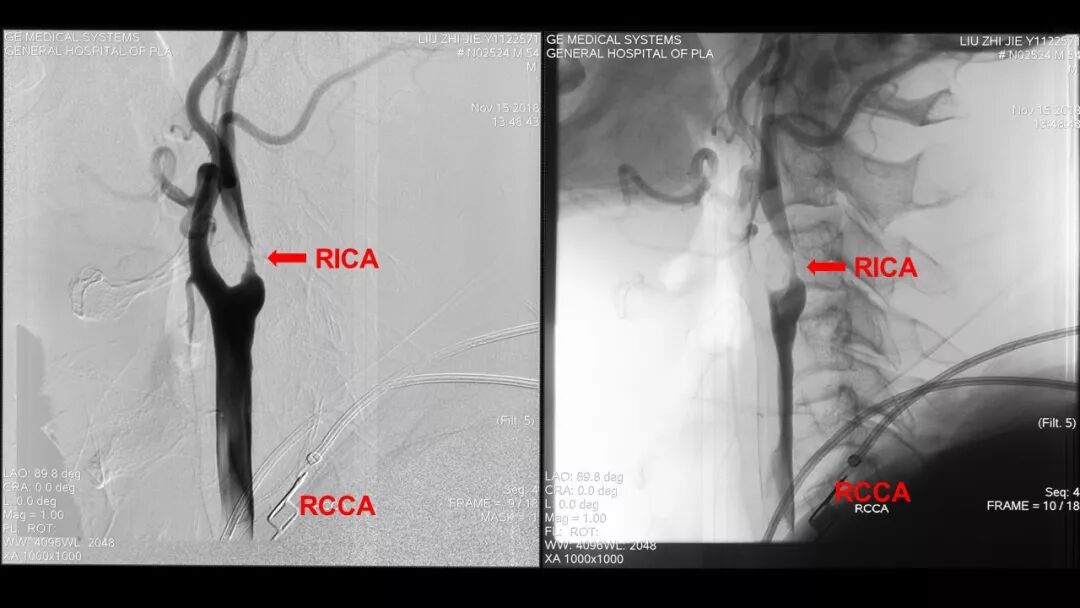

颈动脉粥样硬化性重度狭窄有两种外科处理方式,CEA和CAS(Carotid Artery Stent,支架置入)。统计显示两种方式的治疗效果相差无几。根据临床特点,一小部分病例适合CEA,另一小部分适合CAS,但大部分病例两者均可。但目前我国的现状是CEA:CAS为1:7,而CAS的费用远高于CEA。我国目前经济还处在不发达的状态,而且所需支架依赖进口,同时,CEA手术是一个不难掌握的手术。所以笔者认为,为了减轻社会及家庭负担,也本着环保节能的理念,适合做CEA的患者尽量做CEA,不适合做CEA的再做CAS,这样比较符合我国国情,也期待国产支架的研发与应用。

至于颈动脉内膜切除的相关内容,周定标教授的《颈动脉内膜切除》术中都有详尽的阐述,内容丰富,言简意赅,通俗易懂。现在笔者给大家呈上的是CEA的手术视频,全程基本无删减,是我们手术团队普通手术之一,如实奉献给大家,希望能为CEA手术的推广,年轻医生的手术操作培训尽到微薄之力,也请业内人士批评指正。